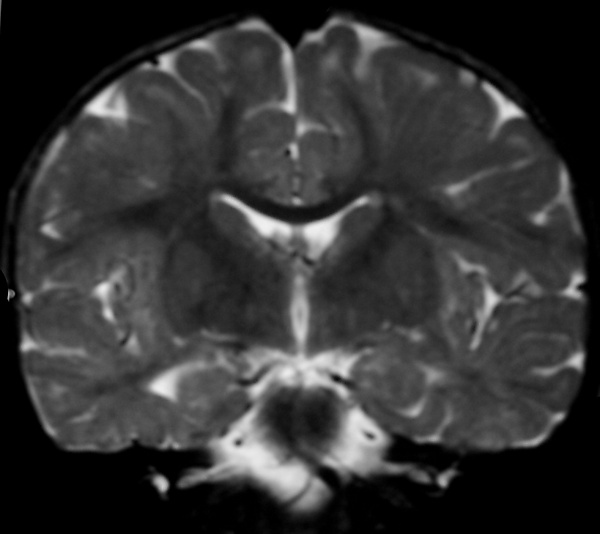

Метахроматическая лейкодистрофия

Метахромати́ческая лейкодистрофи́я (англ. Metachromatic leukodystrophy (MLD), также сульфати́дный липидо́з) — редкое наследственное заболевание из группы лизосомных болезней накопления с аутосомно-рецессивным механизмом наследования нарушения обмена веществ[1]. Данная нозологическая единица из разряда лейкодистрофий (патология роста и/или развития миелиновой оболочки, покрывающей большинство нервных волокон центральной и периферической нервной системы) относится к сфинголипидозам. Характеризуется недостаточностью арилсульфатазы А[2] (цереброзидсульфатазы) — фермента лизосом, участвующего в метаболизме сфинголипидов, что вызывает накопление цереброзида сульфата[1][3].